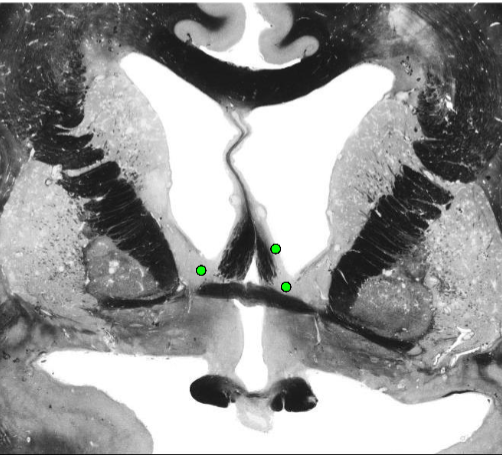

Hippocampal Formation

Hippocampal Formation Components

Hippocampal Formation Afferents and Efferents

Cornu Ammonis

Flow of signals through the hippocampal formation